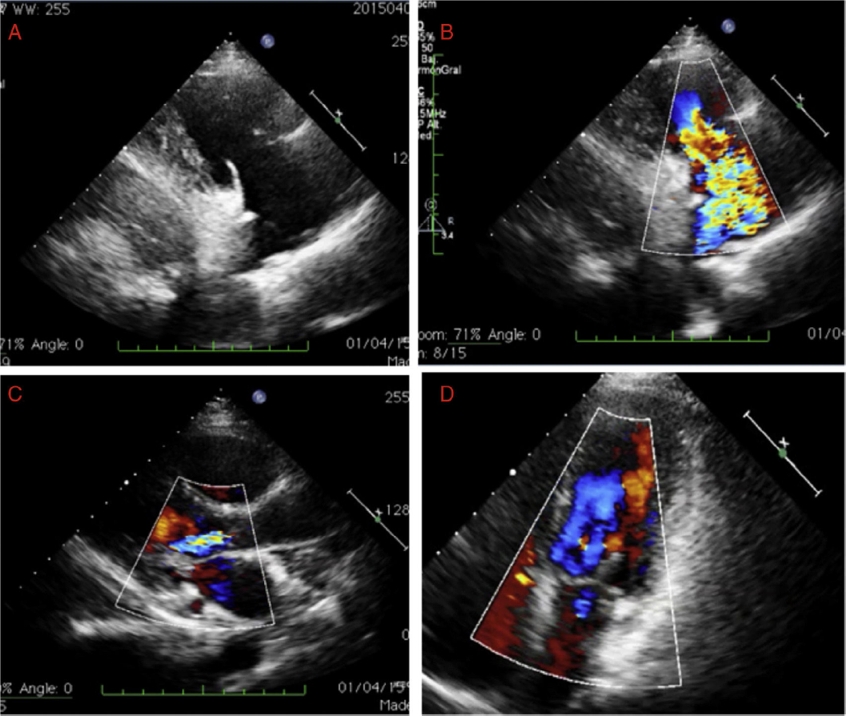

Se trata de una mujer de 48 años sin hábitos tóxicos y con antecedentes personales de hipertensión arterial, hipotiroidismo, trastorno ansioso-depresivo y diarrea crónica con colonoscopia realizada en el mes previo sin hallazgos reseñables. La paciente consultó en nuestra institución por disnea de esfuerzo progresiva, hiporexia y pérdida de peso de 15 kg. En la exploración física destacaban telangiectasias malares, signos de congestión derecha y soplo sistólico II/VI. Se realizó un ecocardiograma transtorácico donde se observó dilatación del ventrículo derecho, aurícula izquierda dilatada de forma moderada y datos de afectación inflamatoria en las válvulas cardíacas: a) tricúspide engrosada sin calcificación e inmóvil en posición de apertura, generando una insuficiencia tricúspide masiva (Figs. 1 A y B); b) mitral engrosada con apertura en cúpula y estenosis moderada e insuficiencia ligera (Fig. 1C); c) válvula aórtica engrosada con apertura en cúpula e insuficiencia ligera (Fig. 1D).

Figura 1 Ecocardiograma transtorácico. Figura 1A: en el plano paraesternal longitudinal de entrada cavidades derechas, se observa una válvula tricúspide con valvas engrosadas y rígidas que no coaptan. Figura 1B: en el estudio Doppler color se observa una insuficiencia tricuspídea severa. Figura 1C: válvula aórtica engrosada y apertura en cúpula con estenosis moderada e insuficiencia ligera. Figura 1D: válvula mitral engrosada y también con apertura en cúpula e insuficiencia ligera.